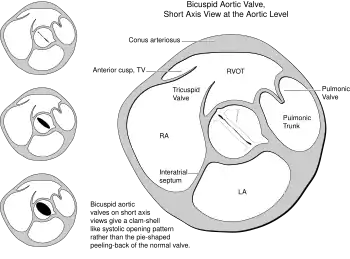

Transesophageal echocardiography- the right side commissure of the bicuspid aortic valve is ruptured -

Heart bicuspid aortic valve diagram